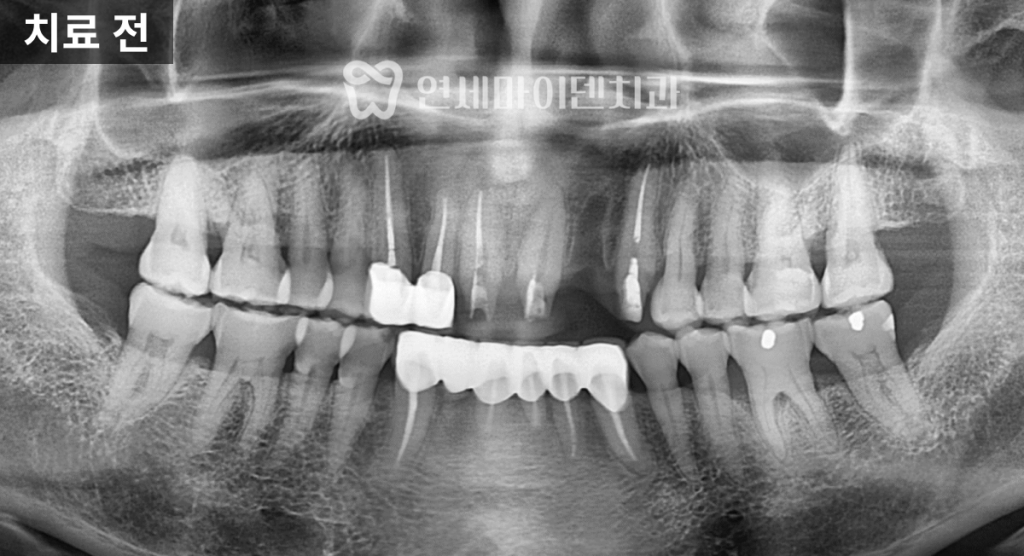

70대 고령 환자의 건강보험 임플란트 케이스입니다.70대 고령 환자 임플란트 진단

이번 케이스는 70대 환자분으로,

어금니 두 개에 임플란트 치료가

필요한 상황이었습니다.하지만 임플란트 치료는

결손 부위만 보고 바로 수술을 결정해서는 안 됩니다.어금니와 앞니 주변의 잇몸 상태,

충치 유무,

그리고 전체적인 교합 관계는

임플란트의 장기적인 안정성과

직결되기 때문입니다.

이번 사례에서도

임플란트가 필요한 부위 외에

다른 치아에서

잇몸 질환과 충치가 함께 발견되었습니다.따라서 이번 치료는

임플란트뿐만 아니라

잇몸 치료와 충치 치료까지

구강 전체를 종합적으로 관리하는 방향으로

계획을 세웠습니다.이처럼 전체적인 구강 환경을 함께 정리해야

임플란트 식립 후에도

치아와 잇몸이 균형을 이루며

오랫동안 건강하게 유지될 수 있습니다.3D 가이드 임플란트 계획